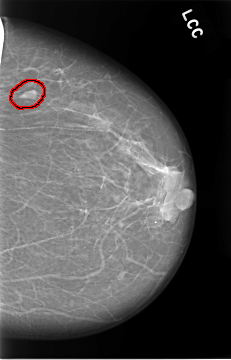

FILE: C_0019_1.LEFT_CC.OVERLAY

TOTAL_ABNORMALITIES 1

ABNORMALITY 1

LESION_TYPE MASS SHAPE OVAL MARGINS CIRCUMSCRIBED

ASSESSMENT 2

SUBTLETY 5

PATHOLOGY BENIGN

TOTAL_OUTLINES 1

BOUNDARY